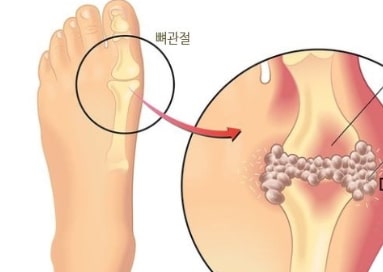

통풍 원인

통풍은 관절 사이에서 통증을 유발하는 관절 질환 중 하나입니다. 사람의 인체는 신체의 대사과정을 통하여 요산이 대산물로 생성이 되게됩니다. 이 요산이 지속적으로 신체의 혈액에 쌓이게 되어 결정화 되면 나타나는 증상을 요산염이라고 합니다. 이 요산이 발가락, 손가락 혹은 무릎 관절에 쌓이게 되면 통증을 유발하는 것입니다. 지속적으로 쌓이게된 요산은 오래 방치할 경우 염증 혹은 관절형태의 변형을 초래할 수 있기때문에 적절한 치료를 하루빨리 권장드리는 바입니다.

통풍 초기증상

통풍의 초기증은 다음과 같습니다.

1. 무릎, 발목, 팔꿈치, 어깨 관절에서 통증이 지속적으로 발생한다.

2. 발가락, 손가락이 부어오르고 통증이 있다.

3. 지속적인 통증으로 인하여 잠에서 종종깨곤한다.

4. 극심한 통증이 발생한 부분에서 붉은빛을 띠면서 부어오른다.

5. 바람만 스쳐도 관절이 쓰라리다.

6. 통증이 심한 부위를 만져보면 울퉁불퉁한 덩어리가 만져진다.